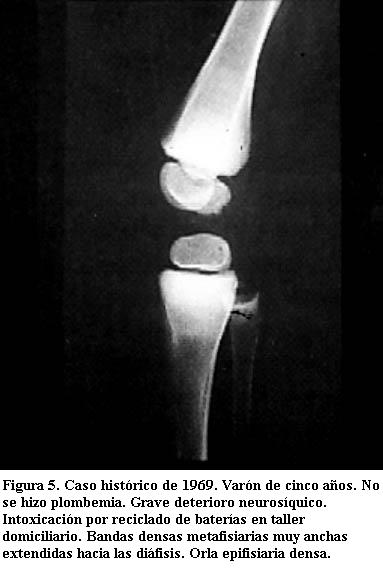

Tienen varios milímetros de espesor y sus límites son nítidos. Son tanto más densas cuanto mayor sea el grado de absorción del metal y tanto más anchas cuanto más haya durado el proceso de absorción (figuras 3, 4 y 5) (5).

Esta manifestación crónica es privativa del niño, por asentar en el cartílago de crecimiento. Es más evidente en el lactante. Su constitución se enlentece a medida que crece el niño (1). Suelen ser bandas únicas, pero pueden ser múltiples; en este último caso, se acompañan de un defecto de la tubulación metafisaria similar al observado en la enfermedad de Pyle y en la osteopetrosis (contorno metafisario parecido al de un frasco de Erlenmeyer) (6).